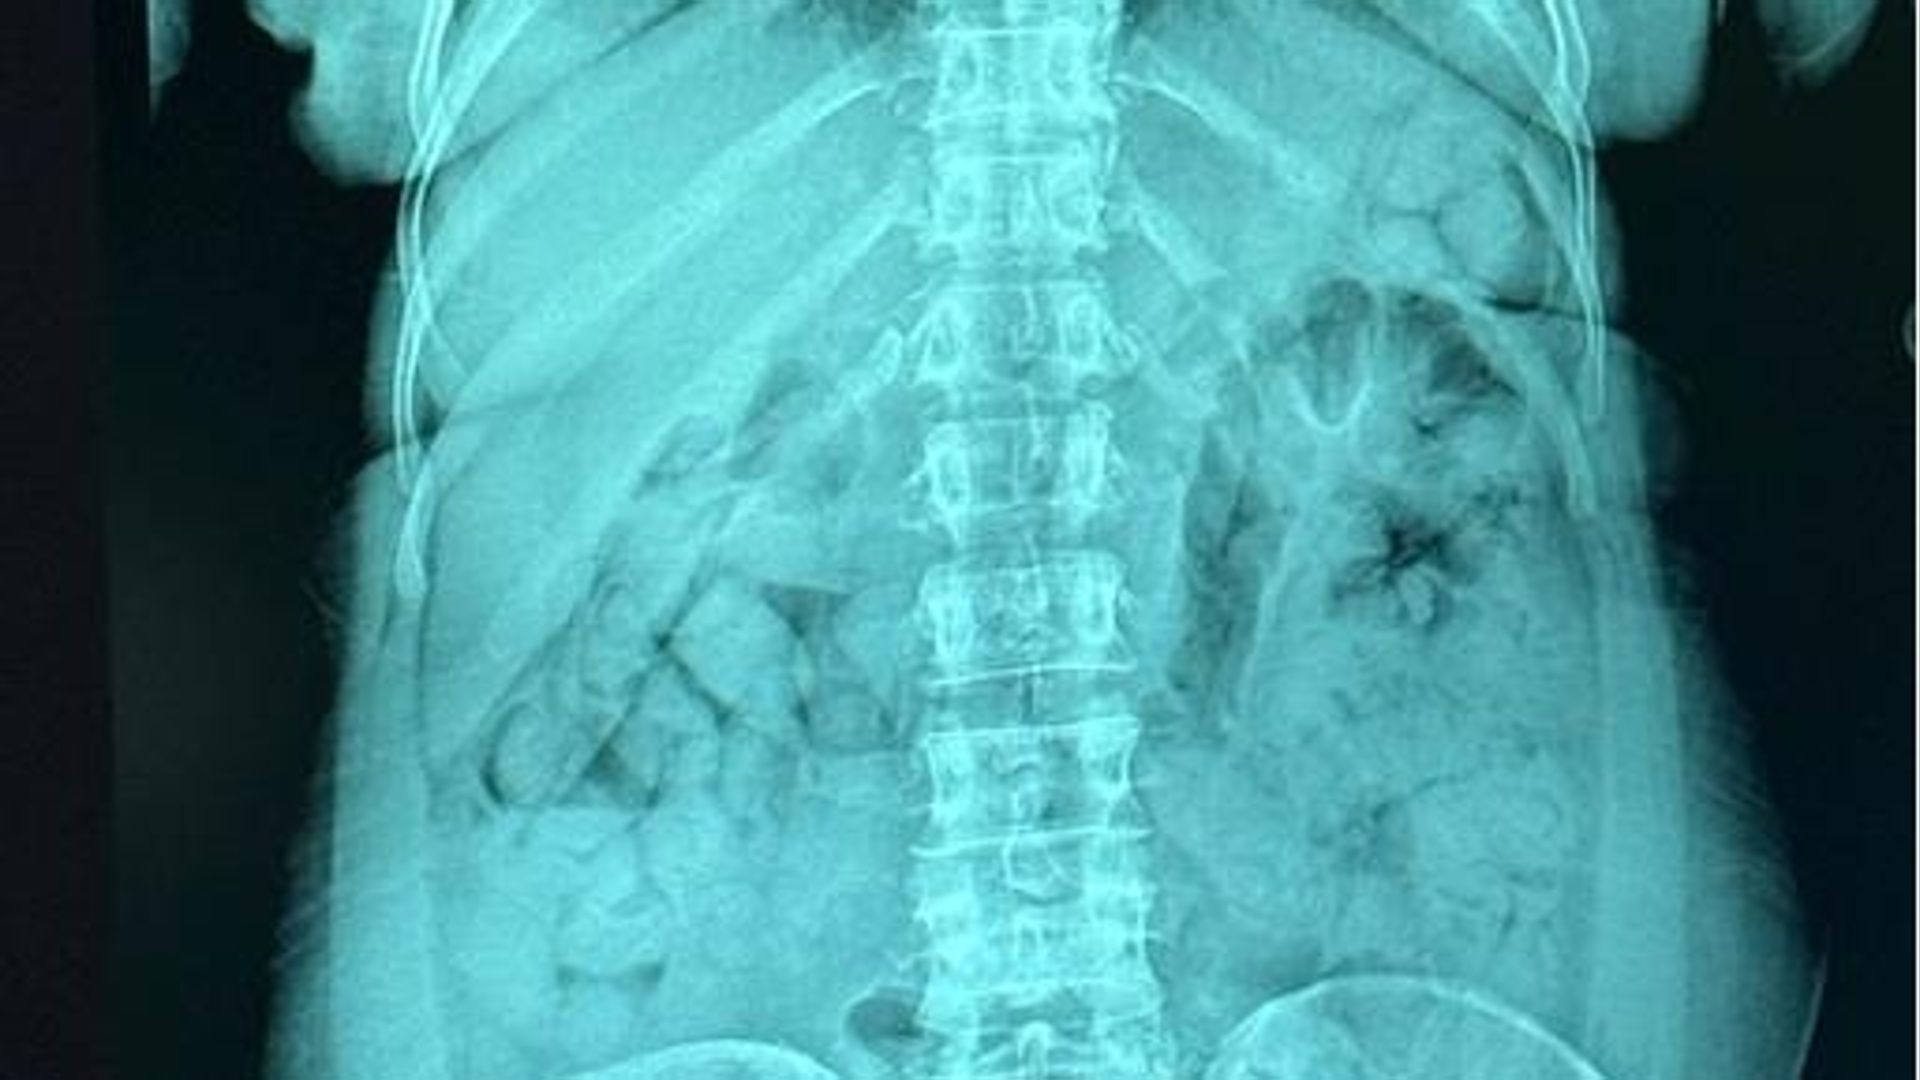

Gli esami e il sequestro

Portata all’ospedale Papa Giovanni XXIII di Bergamo, i radiologi hanno confermato la presenza degli ovuli nello stomaco. Una volta espulsi, sono risultati contenere 1,393 chili di eroina. La sostanza stupefacente è stata sequestrata, mentre la donna è stata arrestata e portata al carcere di Bergamo, a disposizione dell’autorità giudiziaria.